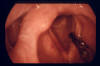

Hyperkeratotischer Tumor der linken Stimmlippe und der Interaryregion